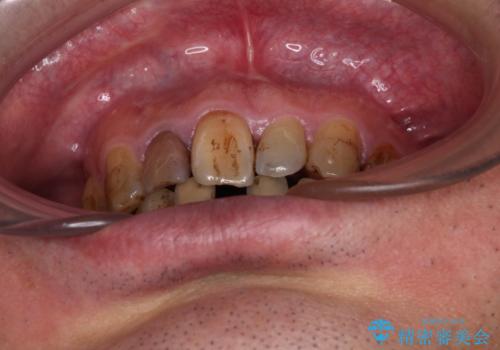

- むし歯治療途中で放置された歯が多く、スペースができたり歯が寄って来たりしているのを気にして来院された患者様です。

上顎前歯もインプラントを希望していらっしゃいましたが、両隣の歯根が近接しており、インプラントは困難と判断したためオールセラミックブリッジによる補綴治療を前提として治療を開始することとしました。